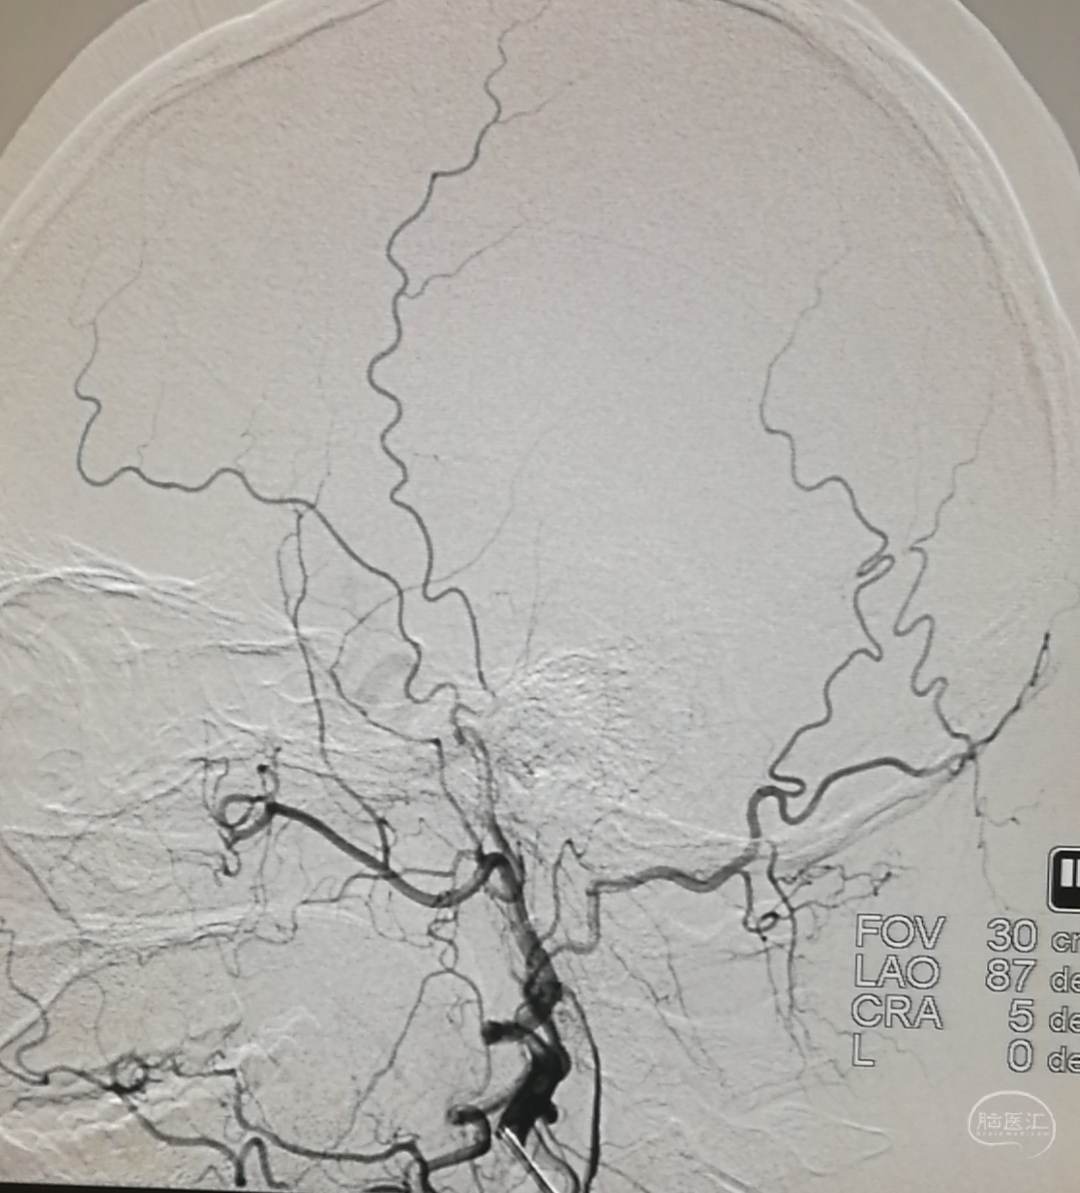

DSA示:左侧大脑前、大脑中动脉闭塞,烟雾样血管形成。

DSA示颞浅A未向颅内代偿。